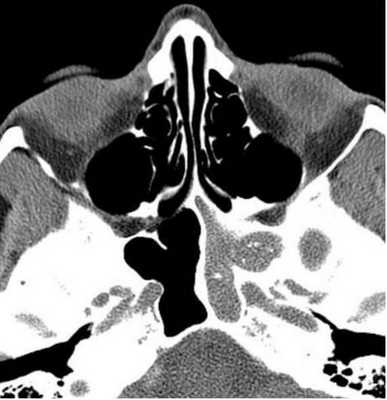

Концентрическая воспалительная гипертрофия ячеек решетчатой кости (указана стрелками)